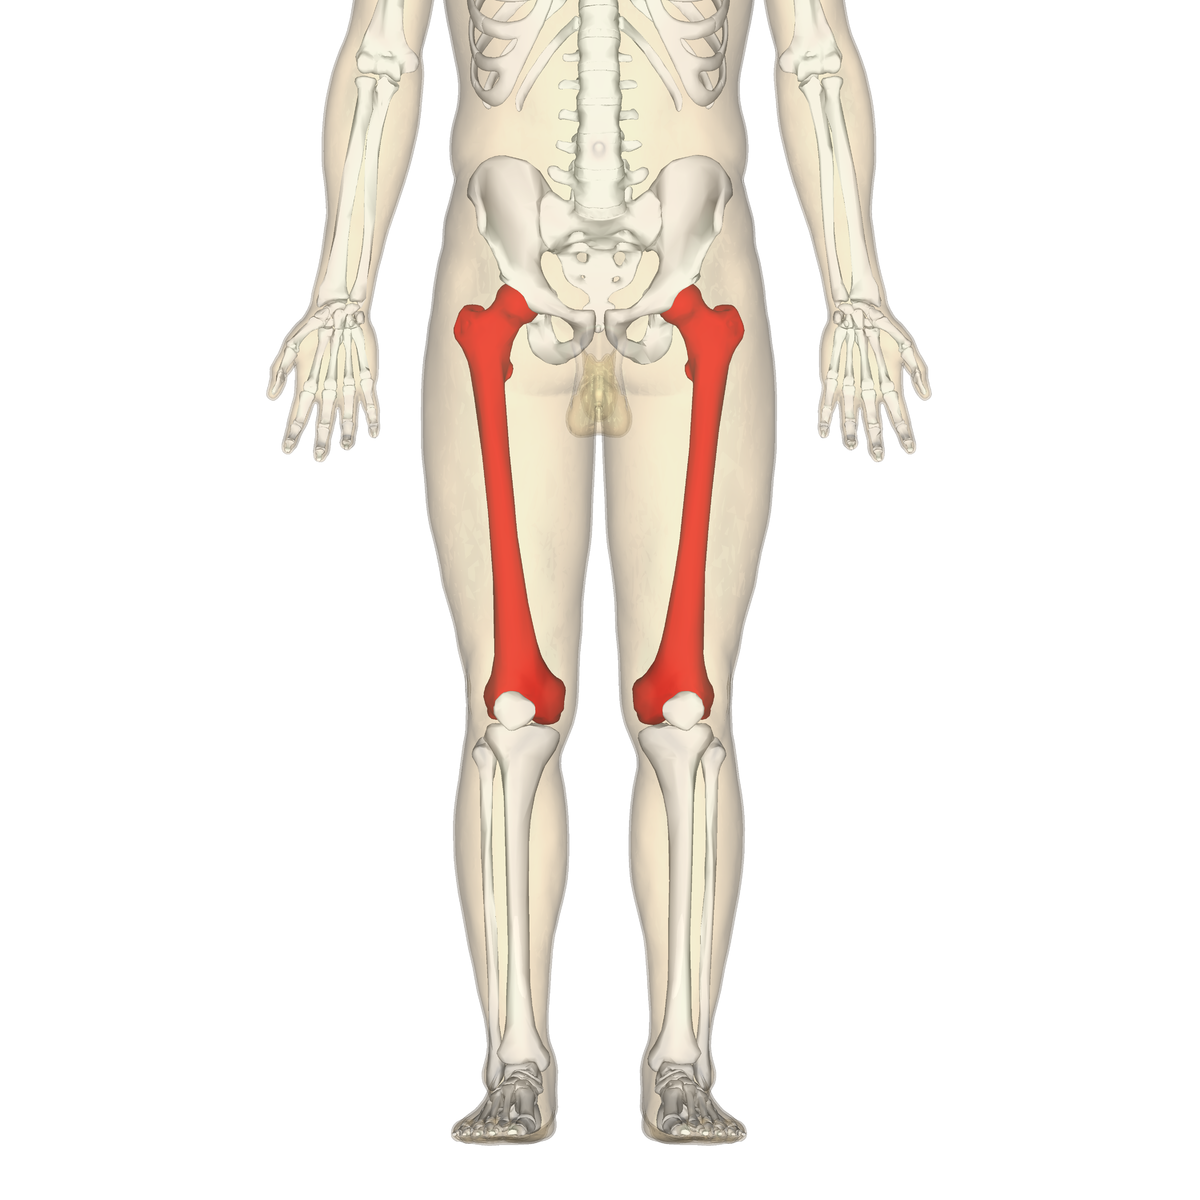

What is this region?

Femur

What is the largest bone in your body?